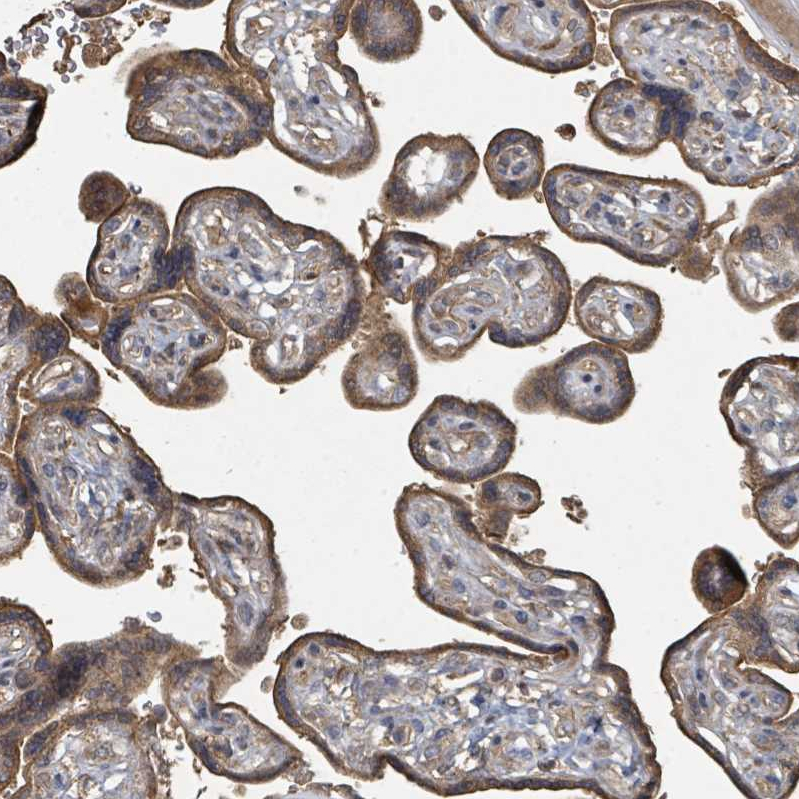

Immunohistochemical staining of human placenta shows strong cytoplasmic positivity in trophoblastic cells.